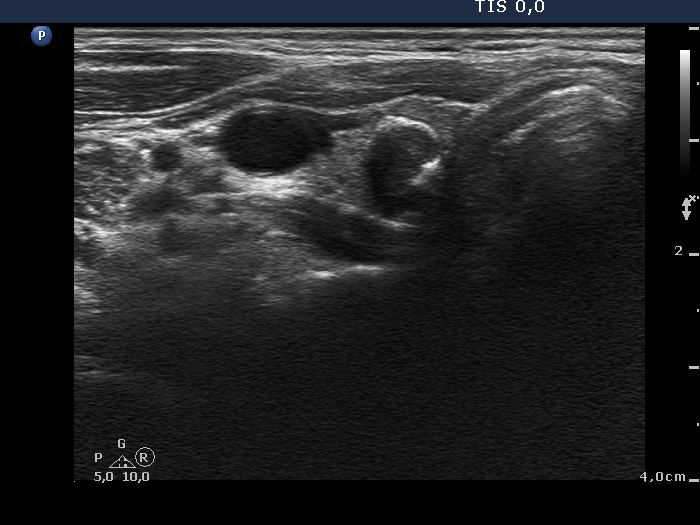

Benign colloid goiter (cytological diagnosis) |

There is a calcification in the dorsal part of the lesion.